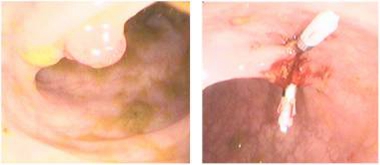

我院消化内科止血治疗又添新项目

消化道出血是消化科的常见病、多发病,也是消化科的急症之一。我院消化科经过多年学习、积累,目前已成功开展了:药物止血、内镜下药物喷洒止血术、内镜下药物注射止血术、三腔二囊管压迫止血术、内镜下药物热活检钳钳夹止血术、食管静脉曲张套扎术止血术,近期又开展了内镜下钛夹止血治疗术。经过临床实践证实:镜下止血术,对绝大多数消化道大出血的患者能够成功进行镜下止血。